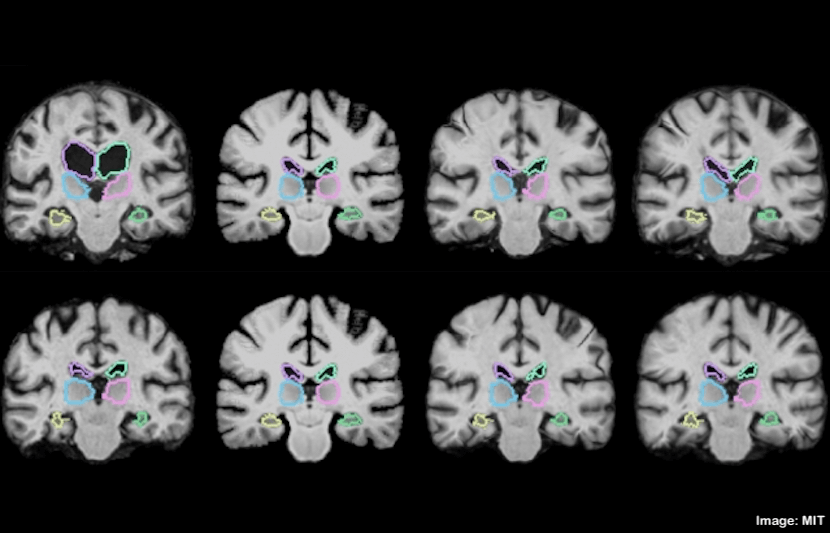

New Algorithm Makes Analyzing Brain Scans 1,000 Times Faster

MIT researchers have built a machine-learning algorithm that can register MRI scans and other 3D images, and compare and analyze them in a matter of seconds. This reduces the traditional runtime of two hours or more down to just a second. Medical imaging, including MRI and CT scans, is not only a medical breakthrough, allowing… Read More